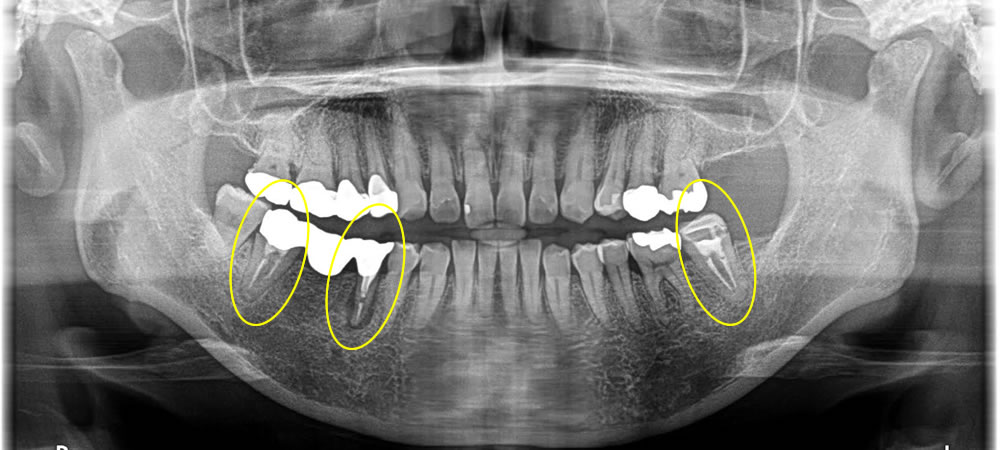

右下のブリッジを除去しインプラント治療を行った症例

▼痛みを感じるブリッジの支台歯と割れた歯を抜歯後、インプラントで治療した症例をご紹介します。

右下ブリッジの部分と左の奥歯が痛むとの主訴で来院された患者さまです。ブリッジの支台歯は感染を起こして痛みが強く出ており、左の奥歯は歯が割れて痛みがあるという状態でした。残しておくリスク、治療方針を話し合い、インプラント治療を行うことに同意を得ました。